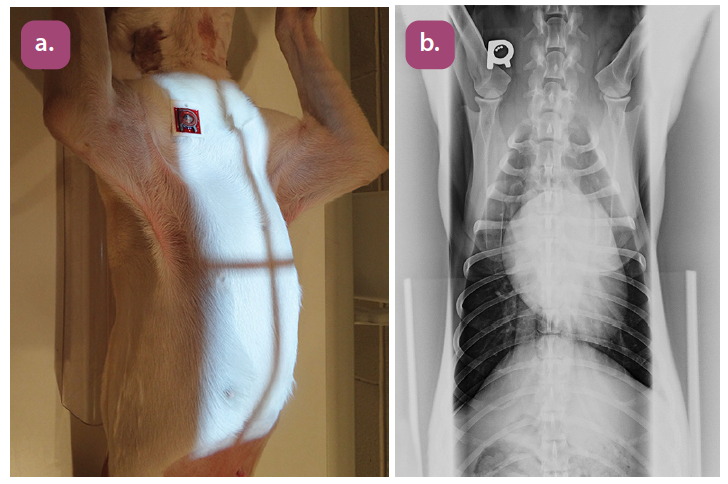

ventrodorsal thoracic spine projection

lateral thoracic spine projection